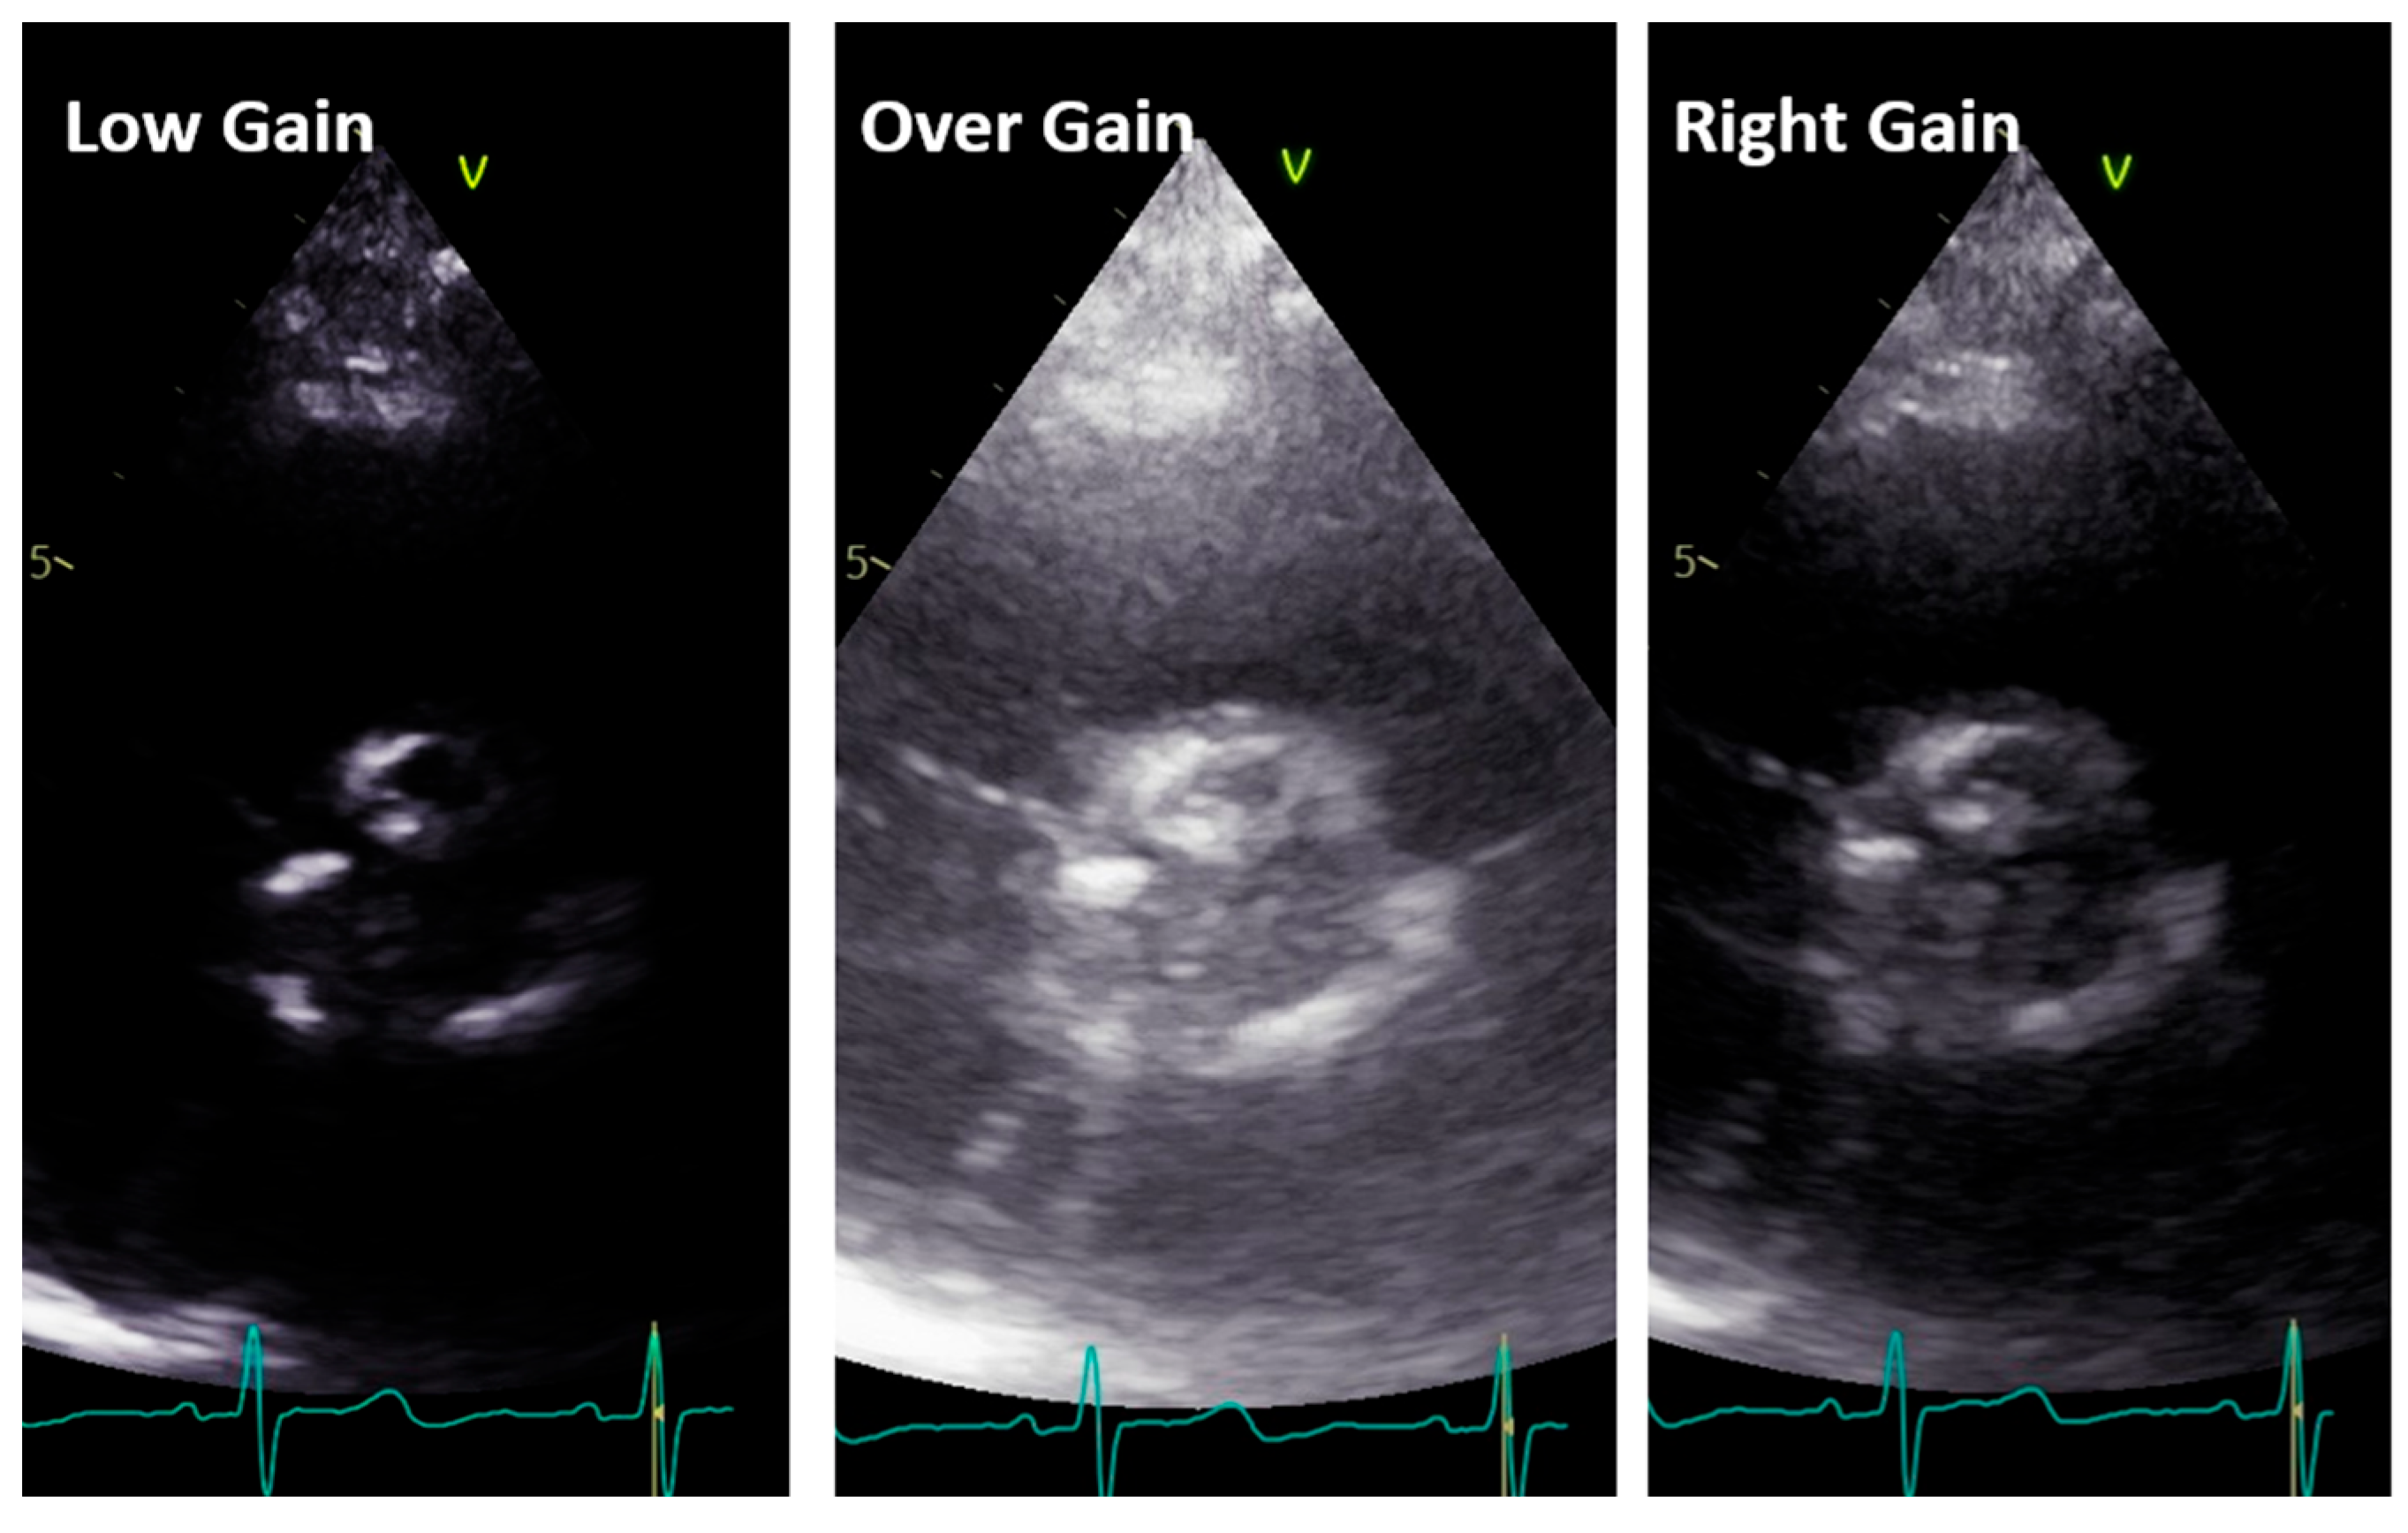

LVOT diameter. The accurate two-dimensional (2D) measurement of LVOT is crucial when assessing AS, as it represents a significant potential source of error in calculating the aortic valve area (AVA) using the continuity equation [15,16,17]. The LVOT measurement is squared within the continuity equation, so any small error in measurement is significantly amplified [18,19]. LVOT diameter should be measured in mid-systole [20]. Mid-systole is the point of the cardiac cycle when the shape of the aortic annulus becomes most circular, and its area becomes maximal. However, for the LVOT, there is no evidence of shape variation from oval to circular throughout systole. Nonetheless, mid-systole should be identified as the frame at half of the total number of frames available between the aortic opening and closure. In this mid-systolic frame, LVOT is measured from the inner edge to the inner edge of the septal endocardium to the anterior mitral leaflet, parallel to the plane of the aortic valve [20]. If a long-axis view is not available, it is not recommended to measure the LVOT from apical views. It is important to recognize that during image acquisition, the parasternal long-axis view provides better axial resolution, whereas the LVOT apical view relies on lateral resolution, which is a limiting factor. It is important to recognize that after the identification of a correct long axis, imaging resolution improvement is fundamental. Axial resolution, as said before, is the most precise of the other two resolutions, lateral and elevational. Thus, quantitative measurements are made most reliably using data derived from a perpendicular alignment. In order to improve axial resolution, higher frequencies should be used. In addition, harmonic imaging is always recommended in that it improves endocardial definition [21]. Gain controls, which adjust the displayed amplitude of the received signals, should be corrected because excessive gain settings can cause “blooming” of the echoes (Figure 3, left panel), leading to a significant underestimation of the LVOT diameter. Conversely, by lowering too much, the gain prevents proper visualization of the anterior endocardium, resulting in an overestimation of the LVOT diameter (Figure 3, right panel).

Figure 6. Low gain (left panel), over gain (middle panel), and right gain (right panel) in the short-axis view along the same patient.